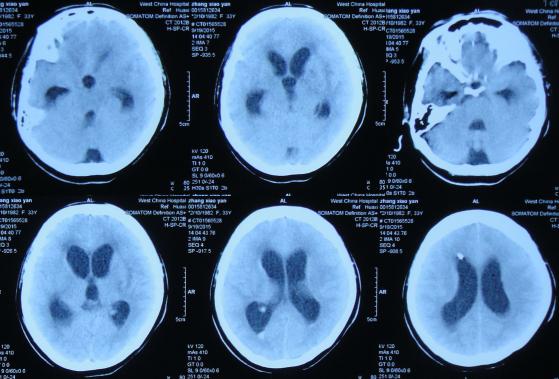

第2家医院治疗3天后即2015年9月7日,查头部CT示侧脑室扩张明显(图-8),次日2015年9月8日,进行了右侧侧脑室钻孔外引流术,查脑脊液细菌培养阴性,PPD(结核菌素)试验阴性。

图-8:2015年9月7日头部CT

第2家医院治疗5天后即2015年9月9日(脑室外引流术后2天),查头部CT示脑室稍有缩小(图-9)。

图-9:2015年9月9日头部CT

第2家医院治疗15天后即2015年9月19日(脑室外引流术后12天),因右侧侧脑室引流管堵塞,脑室再次扩张(图-10)。

图-10:2015年9月19日头部CT

次日2015年9月20日,拔除了右侧侧脑室引流管+左侧侧脑室外引流术,术后当天复查头部CT示脑室缩小(图-11),医生考虑结核性脑膜炎可能性大,给予异烟肼、利福平、乙胺丁醇,吡秦酰胺四联抗结核治疗,同时给予激素、营养支持治疗。

图-11:2015年9月20日头部CT

第2家医院治疗26天后即拔除右侧脑室引流管+左侧侧脑室外引流术后10天即2015年9月30日,查头部CT示脑室再次扩张(图-12)。

图-12:2015年9月30日头部CT

第2家医院治疗34天后即拔除右侧脑室引流管+左侧侧脑室外引流术后18天即2015年10月8日,但右侧肢体活动差,查头部CT示脑室也仍扩张(图-13),考虑引流管再次堵塞,故拔除了左侧侧脑室外引流管,改做腰大池置管持续引流术。

图-13:2015年10月8日头部CT